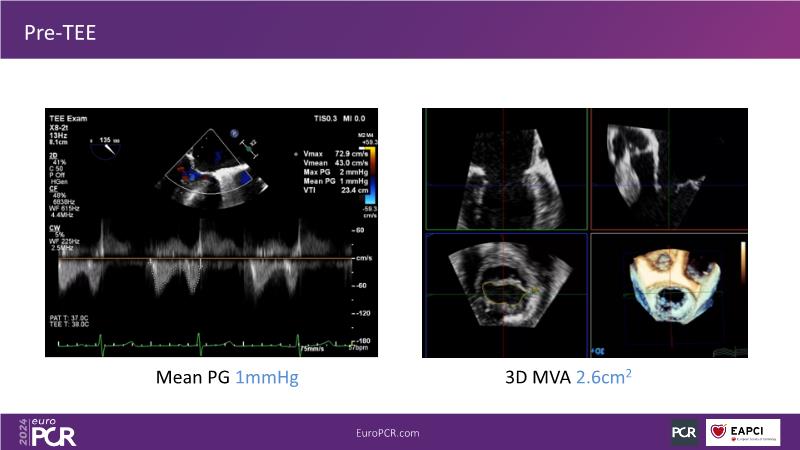

Watch this session to gain insights into the clinical evidence of mitral TEER therapy for the Asian population, learn techniques for implanting a MitraClip in patients with challenging anatomy, and understand how to use the four clip sizes for optimal outcomes. The session also covers educational aspects of clipping in dextrocardia, the benefits of reserve bending of the transseptal needle for tenting and puncture, new steering maneuvers for dextrocardia patients, and the importance of understanding anatomy and collaborating closely with the echo team for success.